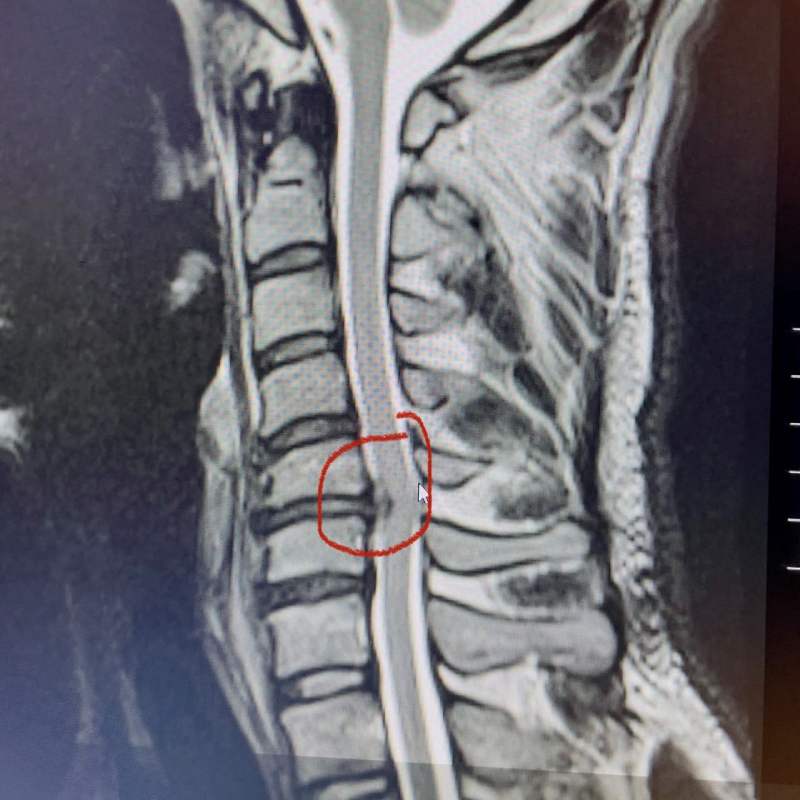

圖/頸椎神經根病變。圖片取自李景亮TWITTER

另一則新聞則是中國籍綜合格鬥選手李景亮,因為頸椎神經根壓迫,可能會被迫中斷職業生涯。李景亮長期已有頸部不適,應是長期練習角力及柔術累積傷害且恢復不足的結果,暫時無法出賽,且有面臨開刀的可能性。